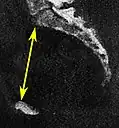

Conjugata vera as measured on sagittal MRI -

Obstetric conjugate, as a measure of the pelvic inlet in the sagittal plane